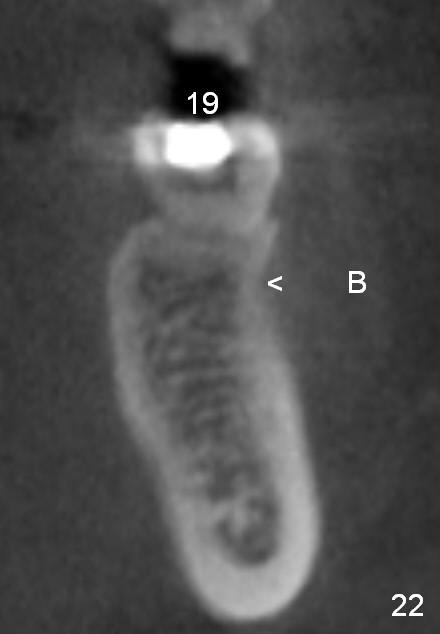

CBCT taken 15 months post cementation shows that the implant is buccally placed (Fig.21 B), associated with possible postop buccal plate resorption (as compared to Fig.23 (coronal section of the site of #19). The buccal plate is not only thinner than the lingual one, but also concave (Fig.22 <). The tooth center (i.e., septum; Fig.23 T) is more buccally located than the center of the basal bone (B). Considering the denser bone lingually, the initial osteotomy should be more lingually (^). If the implant develops infection, it will be replaced by a more lingually placed implant (Fig.24 green).